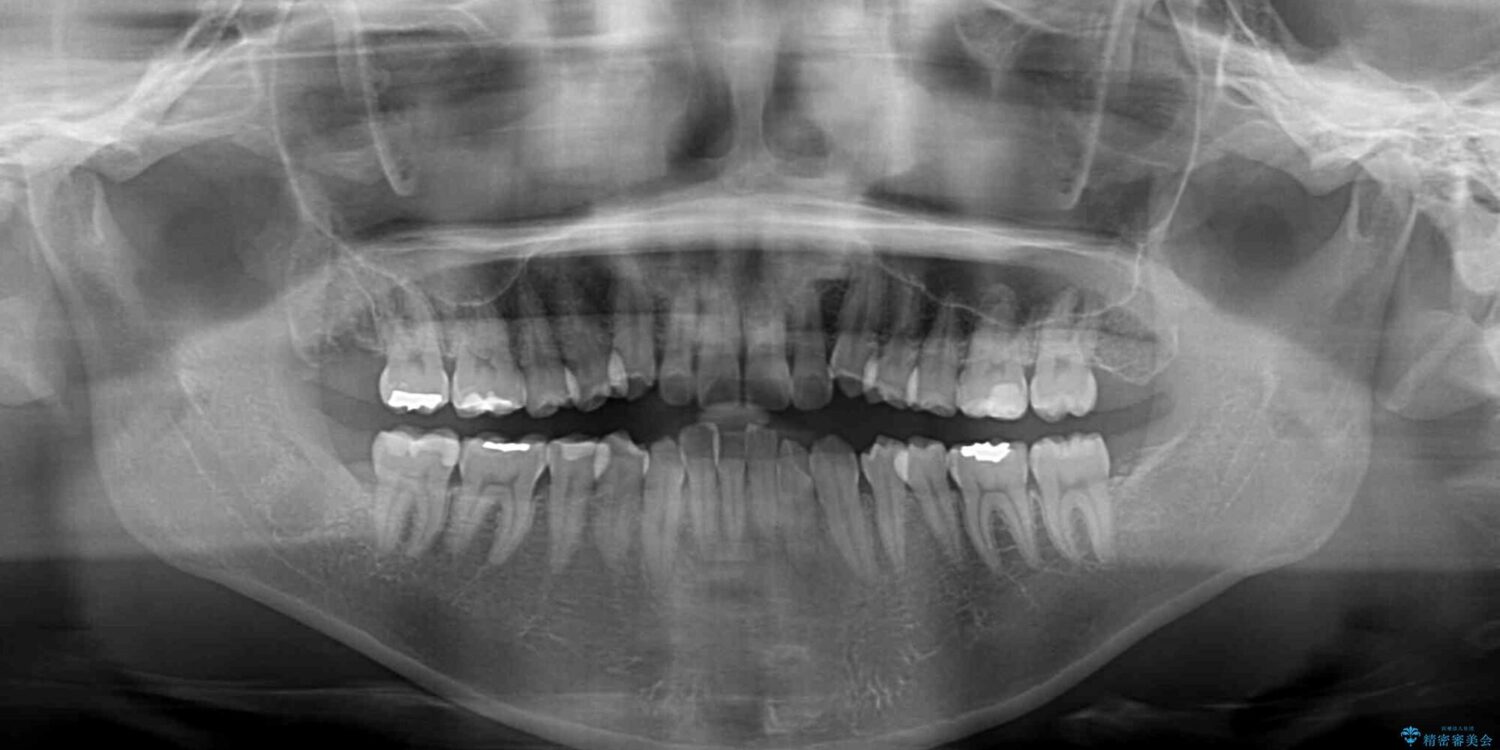

前歯の叢生と八重歯を気にして来院された患者様です。

目立たない装置を希望とのことで、インビザラインにて矯正治療を行うこととしました。

インビザライン単体で改善することも可能ですが、八重歯とその後方にある歯列を確実移動させないと、上下正中がずれてしまう可能性があります。

インビザライン単体での治療ではなく、カリエール・ディスタライザーという補助装置を併用して、より確実性を上げることとしました。

補助装置で八重歯を解消しながら、並行してインビザラインで歯列を整えることとしました。

カリエールディスタライザーを併用したことで、すっきりとした口元になり、上下の正中を合わせることができました。